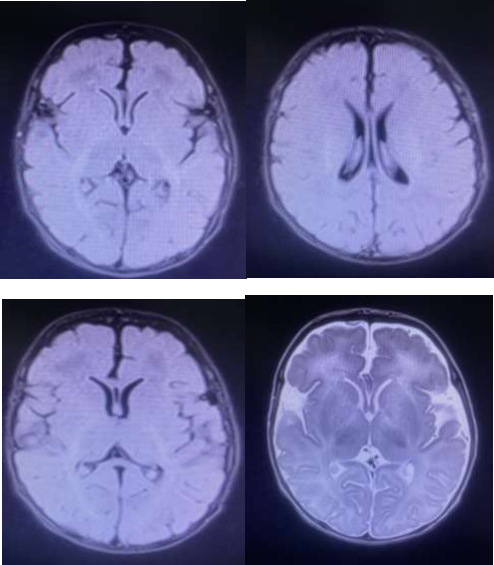

Figure 1: Simple Brain Resonance Images

Simple brain MRI that evidences occupation of the occipital horns of the lateral ventricles that presents restriction in diffusion and there are also foci of restriction in the subarachnoid space in the frontal, temporal and left parietal convexities, as well as the interhemispheric sulcus. Focal hyperintensity that presents diffusion restriction in the knee of the left internal capsule of 4 mm. Rest of the brain parenchyma with signal intensity appropriate for age. Central midline. Turkish chair with usual appearance. Normal sized ventricular system. Vascular structures with signal void. Opinion: The findings described are attributed to meningitis with ventriculitis and small ischemic lesion in the internal capsule due to a probable vasculitic focus secondary to an infectious process.